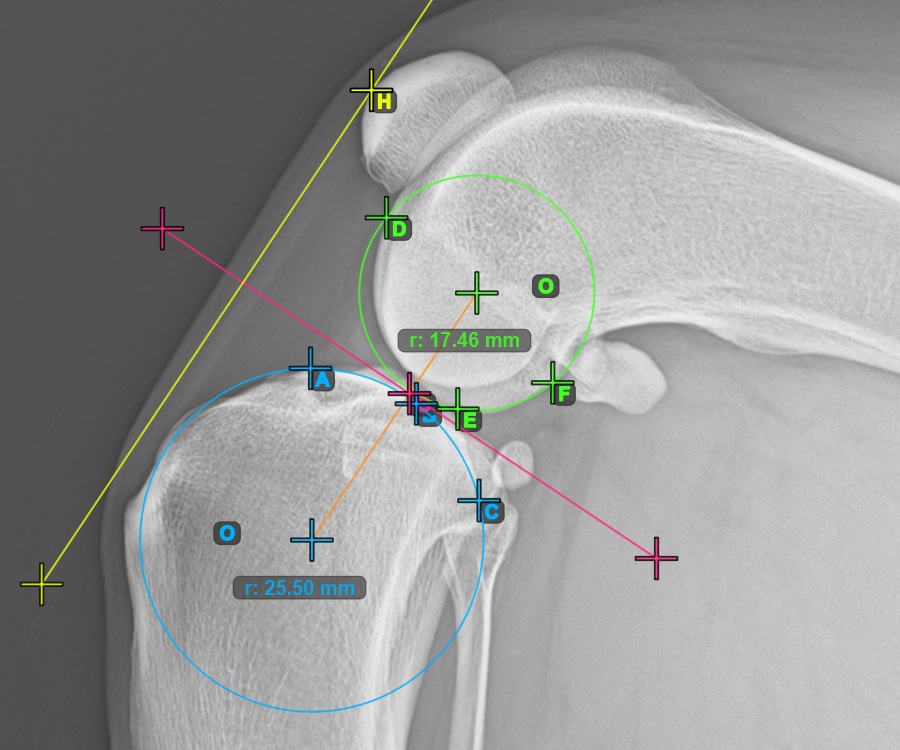

The image below represents a typical placement of the three points on the Condylus Femoris.

![]()

Continue by marking the three points on the articular surface of the Condylus Femoris.

Mark the three points on the main condylus of the femoral bone (Condylus Femoris). Regardless of the order, make sure to mark the most cranial point, the most caudal point and the midpoint of the Condylus Femoris. A circle will be automatically constructed based on the three placed points.

Mark one point in front of the joint on the common tangent between the two circles. A line will be drawn automatically through the marked point.